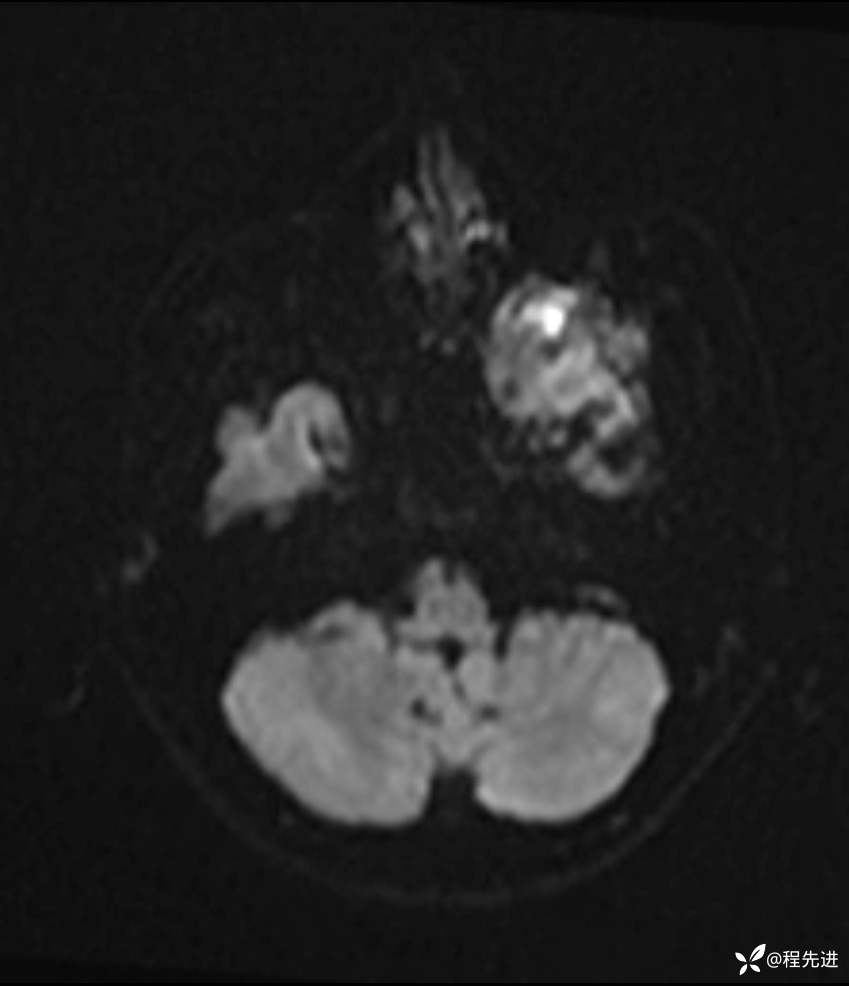

DWI: